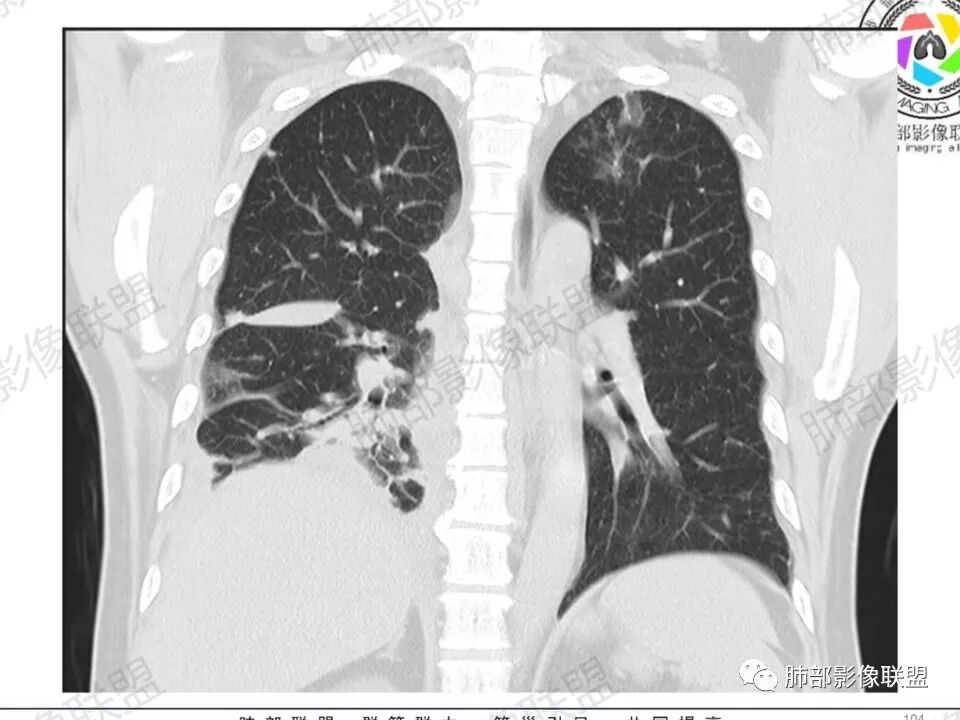

双肺多发结节,胸膜下为主,部分可见空洞。左肺上叶尖后段结节较大,分叶毛刺,周围可见长条索及小斑片影,内空洞比较光滑,内侧壁可见支气管通过。右肺下叶后基底段不张实变,后侧积液,右侧水平裂积液,右侧膈胸膜纵膈胸膜增厚积液,右侧侧胸膜肥厚,考虑1:一元金葡。2二元:金葡,左肺上叶结核。

尘缘: @赵永兵 内蒙巴市临河妇幼影像科 左上肺也是胸膜下(胸膜顶下)的SPE。

@赵永兵 内蒙巴市临河妇幼影像科 支气管是从旁边经过,所以不是空洞,是胸膜下的脓毒栓。如果是结核空洞,应该与支气管相通(因为结核没有血播感染表现的时候,来源是气道,空洞应该与支气管相通),所以支气管从旁边经过,这病灶又在胸膜下,周围也没有干酪坏死。当然是SPE了。

中年男性,左手中指及胸壁疼痛伴发热来诊,影像见双肺多发结节,胸膜下分布为主,部分结节可见空洞,边缘模糊。左肺上叶尖后段结节较大。右肺下叶后基底段不张实变,右侧叶间裂及右侧胸腔积液,右侧侧胸膜肥厚。考虑金葡菌感染,血播SPE。

胸膜下为主多发结节,边缘光滑

伴随楔形影,支气管壁不增厚

空洞内壁光滑,偏心厚壁空洞,张力高

支持血道来源感染性病变,金葡菌肺炎首选